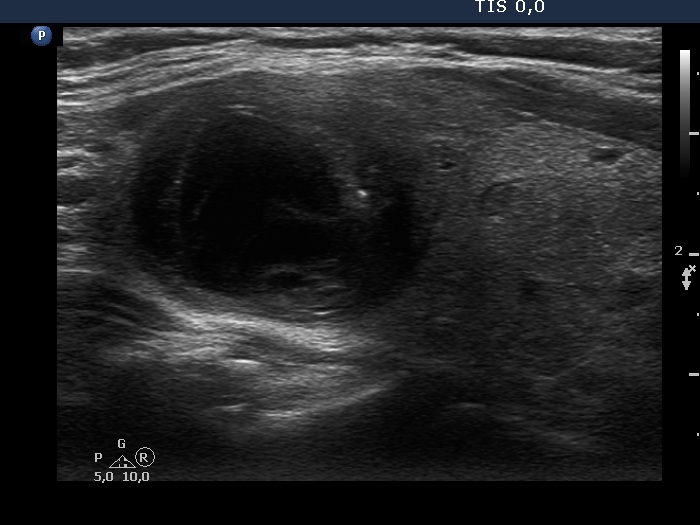

Ultrasonography. The thyroid was echonormal. There was a mixed moderately hypoechogenic-cystic nodule in the right lobe. The lesion presented various intranodular hyperechogenic granules including back wall figures, non-specific granules and a few typical comet-tail artifacts. There were other, difficult-to-classify bright granules. The latter could be either comet-tail artifacts or microcalcifications. There were several moderately hypoechogenic lesions in the left lobe.

Comments. This case illustrates the difficulty of distinguishing comet-tail artifact from microcalcification. The relevance of this differentiation lies in the consequences, the former is found almost always in benign lesions while the presence of microcalcifications increases the likelihood of papillary carcinoma.